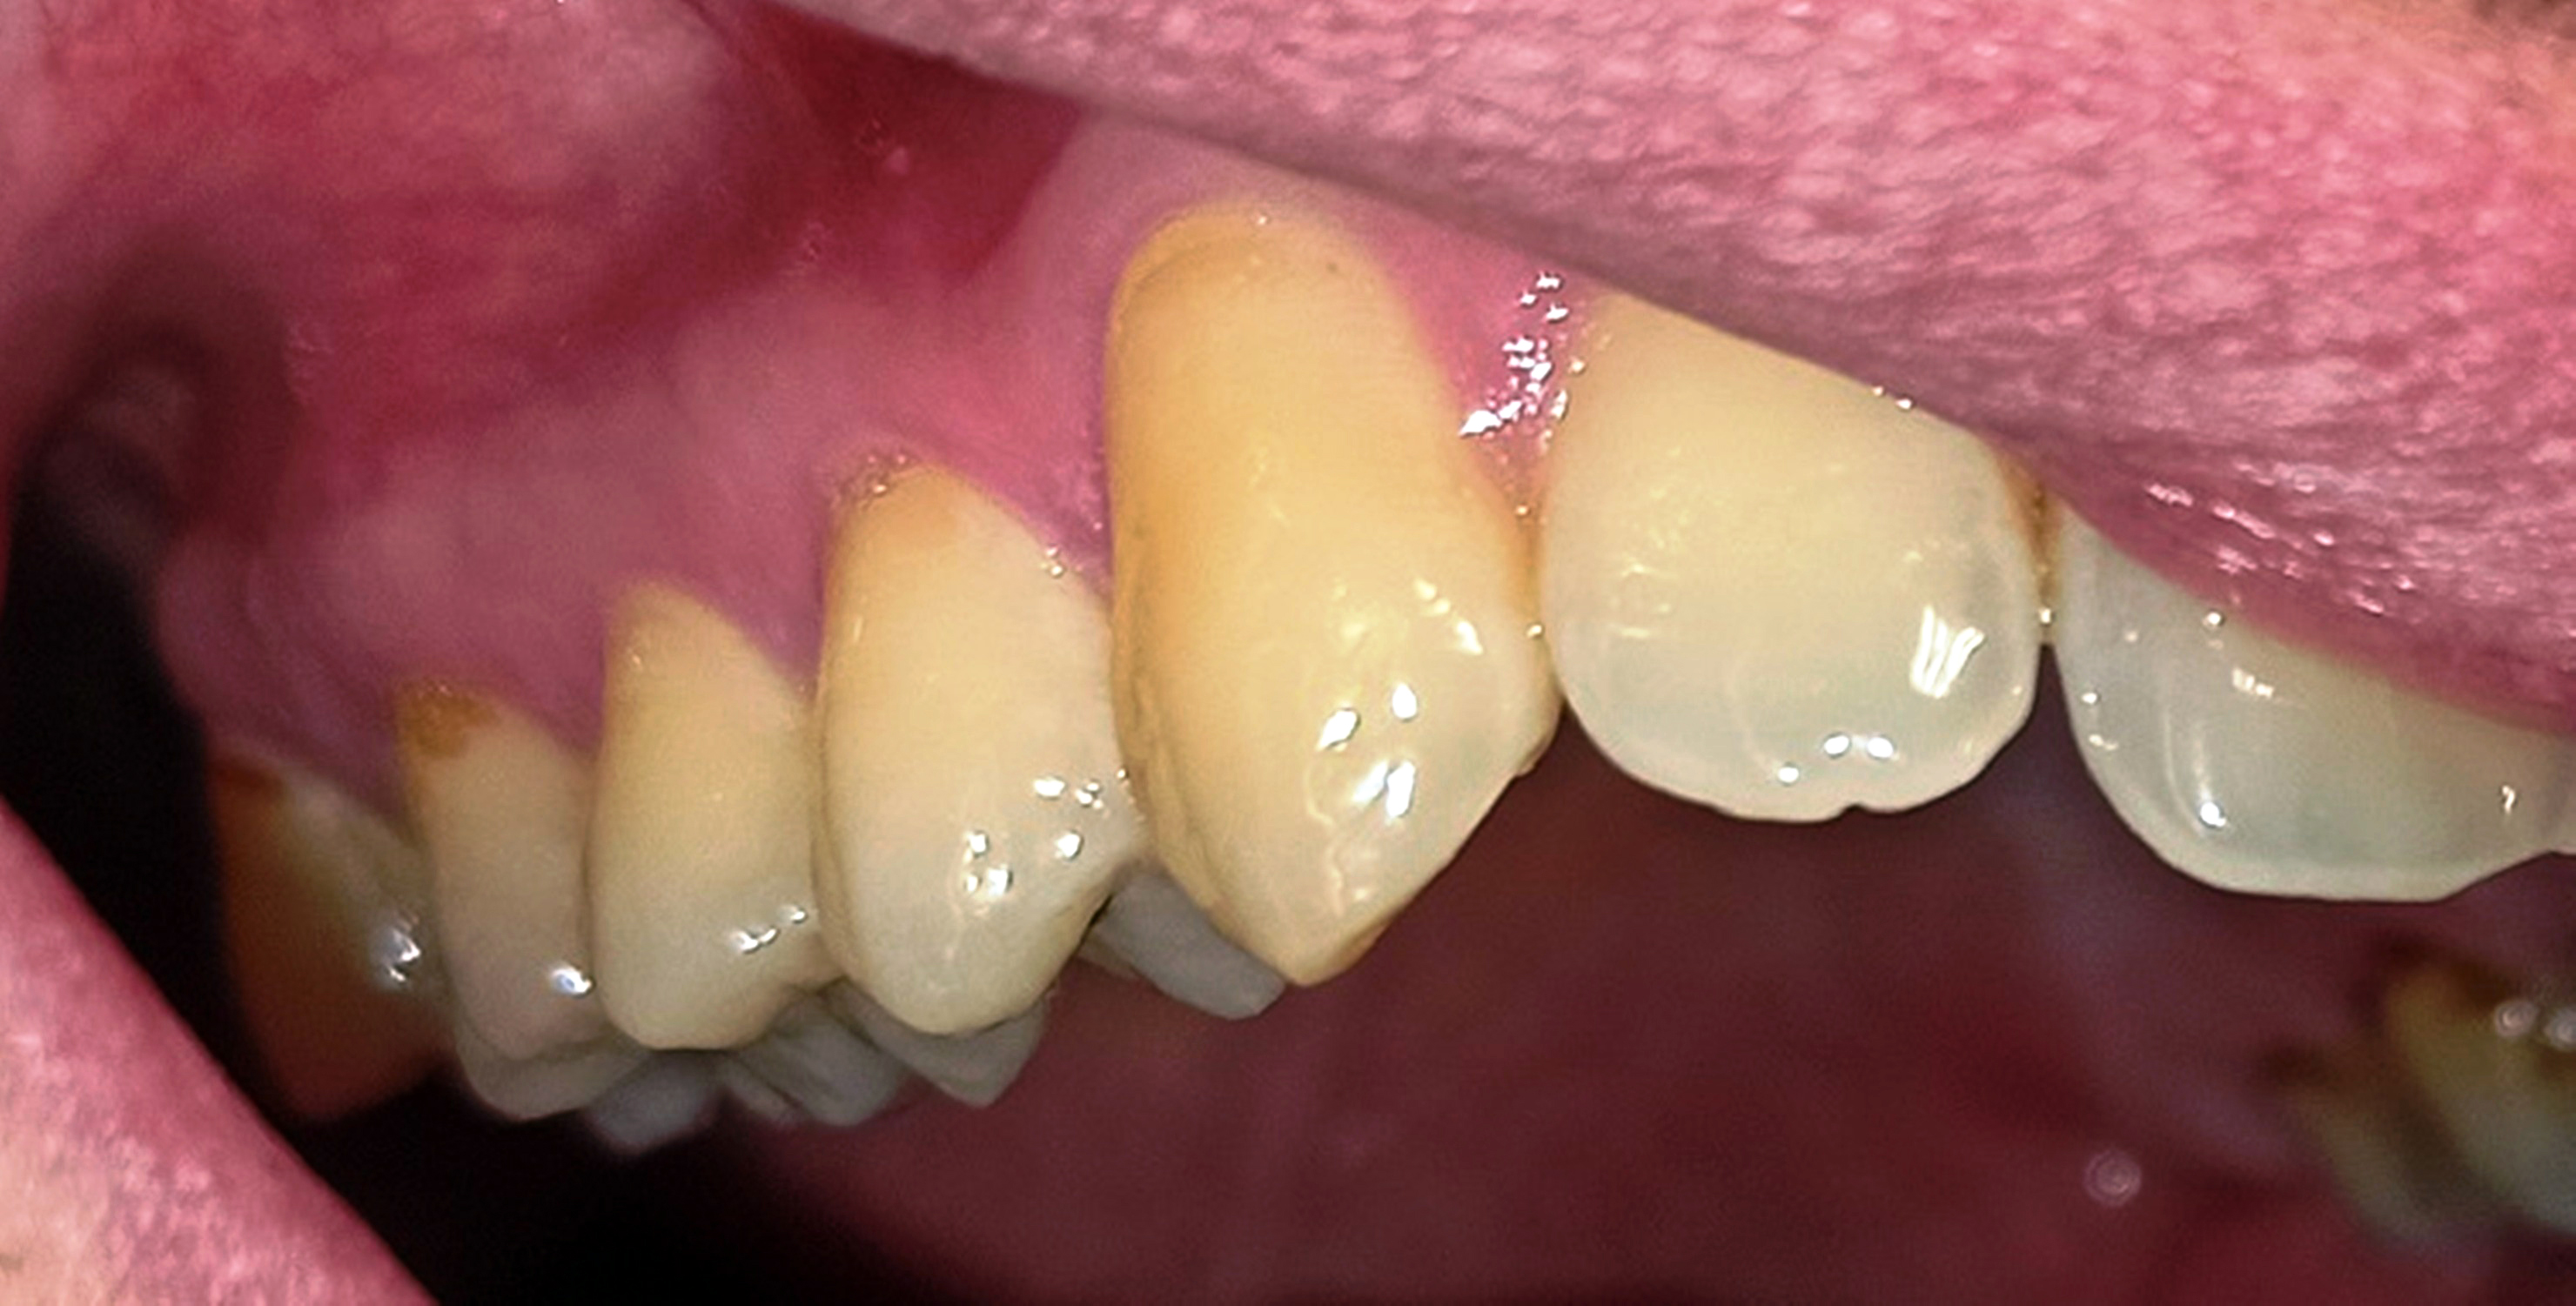

Nach dem Ort der Läsion wird die FP in periphere und zentrale FP eingeteilt. Erstere entsteht durch komplette oder inkomplette Schädigung der motorischen Fasern des Nucleus nervus facialis und betrifft die gesamte ipsilaterale Gesichtshälfte (11); (Abb. 1a-c). Letztere entsteht infolge einer Läsion innerhalb der kortikonukleären Bahn und tritt kontralateral zum Schädigungsort ohne die Beteiligung der Stirnmuskulatur auf (11). Nach der Dauer der Schädigung wird eine chronische von einer akuten FP differenziert. Als Übergang wird ein Zeitraum von drei bis sechs Monaten definiert. Das Hauptsymptom der akuten Parese ist die schlaffe, einseitige Unbeweglichkeit der Gesichtsmuskeln (4). In mindestens 30 % der akuten Fälle kommt es zu keiner vollständigen Heilung. Stattdessen wird eine fehlerhafte Reinnervation mit erhöhter und fehlkoordinierter Muskelaktivität beobachtet (12). Man spricht dabei von einem postparalytischen fazialen Syndrom. Das eindrucksvollste Symptom dieses Syndroms sind Synkinesien, also die pathologischen Mitbewegungen verschiedener physiologisch getrennter Muskeln. So beschreiben zum Beispiel oro-oculäre Synkinesien eine Mitbewegung der M. orbicularis oculi bei Mundbewegungen (13).

Innerhalb der Gruppe der Patienten mit Fazialisparese wurde außerdem ein Vergleich der Mundgesundheit zwischen beiden Mundhälften durchgeführt. Dabei wies die paretische Seite eine signifikant höhere Plaque-Kontamination, mehr Blutungen und höhere PSI-Werte auf als die nicht paretische Seite (Tab. 3). Die Plaque-Kontamination war in Bezug auf den API auf der paretischen Seite um 10,9 % (p = 0,004) höher als auf der nicht paretischen Seite. Ebenso wiesen die vestibulären Zahnoberflächen der paretischen Seite mehr Biofilm auf als die der nicht paretischen Seite (p = 0,002; s. Tab. 3, Abb. 2a und b). Dabei war der Unterschied bei den männlichen Patienten (0,8 vs. 0,5; p = 0,001) größer als bei den weiblichen Patienten (0,6 vs. 0,4; p = 0,002). Außerdem wurde bei Patienten mit rechtsseitiger Fazialisparese ein größerer Seitenunterschied (0,7 vs. 0,5; p < 0,001) dokumentiert als bei Patienten mit linksseitiger Fazialisparese (0,5 vs. 0,4; p = 0,043). Ursächlich erschien die Händigkeit der Patienten. Während bei Patienten mit linksseitiger Fazialisparese die Erkrankung auf der für Rechtshänder besser zu reinigenden Mundhälfte vorlag, waren rechtshändige Patienten mit rechtsseitiger Fazialisparese einer doppelten Belastung ausgesetzt (18). Die Gingivablutung nach Sondierung war auf der paretischen Seite ebenfalls signifikant höher als auf der nicht paretischen Seite (s. Tab. 3). Das spiegelte sich sowohl bei den Werten des SBI (s. Tab. 3, Abb. 3) als auch bei den Werten des PBI (s. Tab. 3, Abb. 4a und b) wider. Die Sondierungstiefen waren auf der paretischen Seite im Vergleich zur nicht paretischen Seite tiefer und der Attachmentverlust war höher. Dabei konnte jedoch kein signifikanter Unterschied nachgewiesen werden. Der mittlere PSI erreichte auf der paretischen Seite signifikant höhere Werte als auf der nicht paretischen Seite (p = 0,032; s. Tab. 3), was auf eine schlechtere Gingivagesundheit hinweist. Darüber hinaus war die Prävalenz unbehandelter kariöser Läsionen auf der paretischen Seite höher als auf der nicht paretischen Seite (s. Tab. 3). Ein Fallbeispiel illustriert eindrucksvoll die Unterschiede zwischen der kariesfreien nicht paretischen Seite und der paretischen Seite mit multiplen aktiv kariösen Läsionen (Abb. 5a und b). Zusätzlich wies die paretische Seite eine höhere Anzahl an Restaurationen auf als die nicht paretische Seite (s. Tab. 3). Hinsichtlich des Zahnsteinbefalls wurden auch im Seitenvergleich der Mundhälften keine signifikanten Unterschiede zwischen den paretischen und den nicht paretischen Seiten festgestellt. Im Einzelfall wurden jedoch eindrucksvolle Unterschiede zwischen den Mundhälften deutlich (Abb. 6a und b).